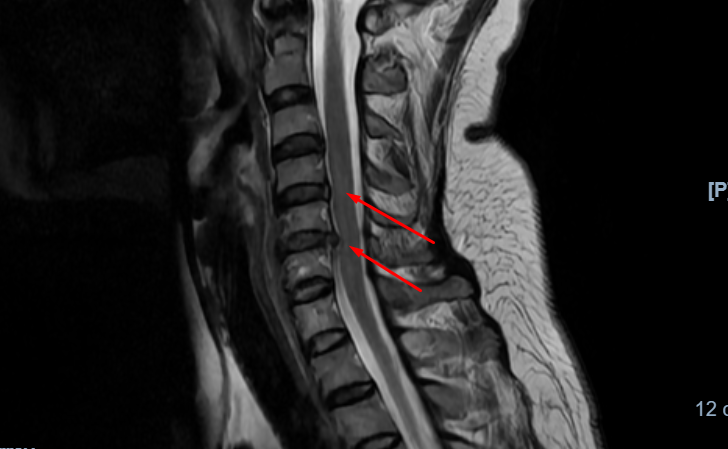

Trực tiếp thăm khám cho bệnh nhân Thái, PGS.TS.BS Hà Kim Trung (Chuyên gia phẫu thuật thần kinh - cột sống - BVĐK Hồng Ngọc) chia sẻ: “Trên phim chụp cộng hưởng từ có thể thấy, vòng xơ đĩa đệm C4/5 rách toàn phần, bệnh nhân thoát vị đĩa đệm đa tầng C3/4, C4/5, C5/6 kèm hẹp cột sống cổ và chèn ép tủy, không còn khả năng điều trị bảo tồn, có nguy cơ cao bại liệt nếu không điều trị kịp thời. Tối ưu nhất là phẫu thuật lấy toàn bộ đĩa đệm C4/5, C5/6 và vòng xơ bị rách, sau đó kết hợp cột sống cổ bằng nẹp vis, với trường hợp này có thể can thiệp phẫu thuật thông qua đường mổ phía trước cổ.”

| Thoát vị đĩa đệm đa tầng C3/4, C4/5, C5/6 kèm hẹp cột sống cổ và chèn ép tủy |